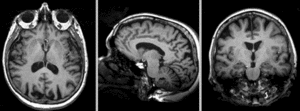

Registration Results

Exam 2 co-registered Exam 1 co-registered: FLAIR and T2 aligned with T1

Exam 2 aligned to Exam 1 Exam 2 aligned to Exam 1 (showing FLAIR and T2 of exam 2 also)